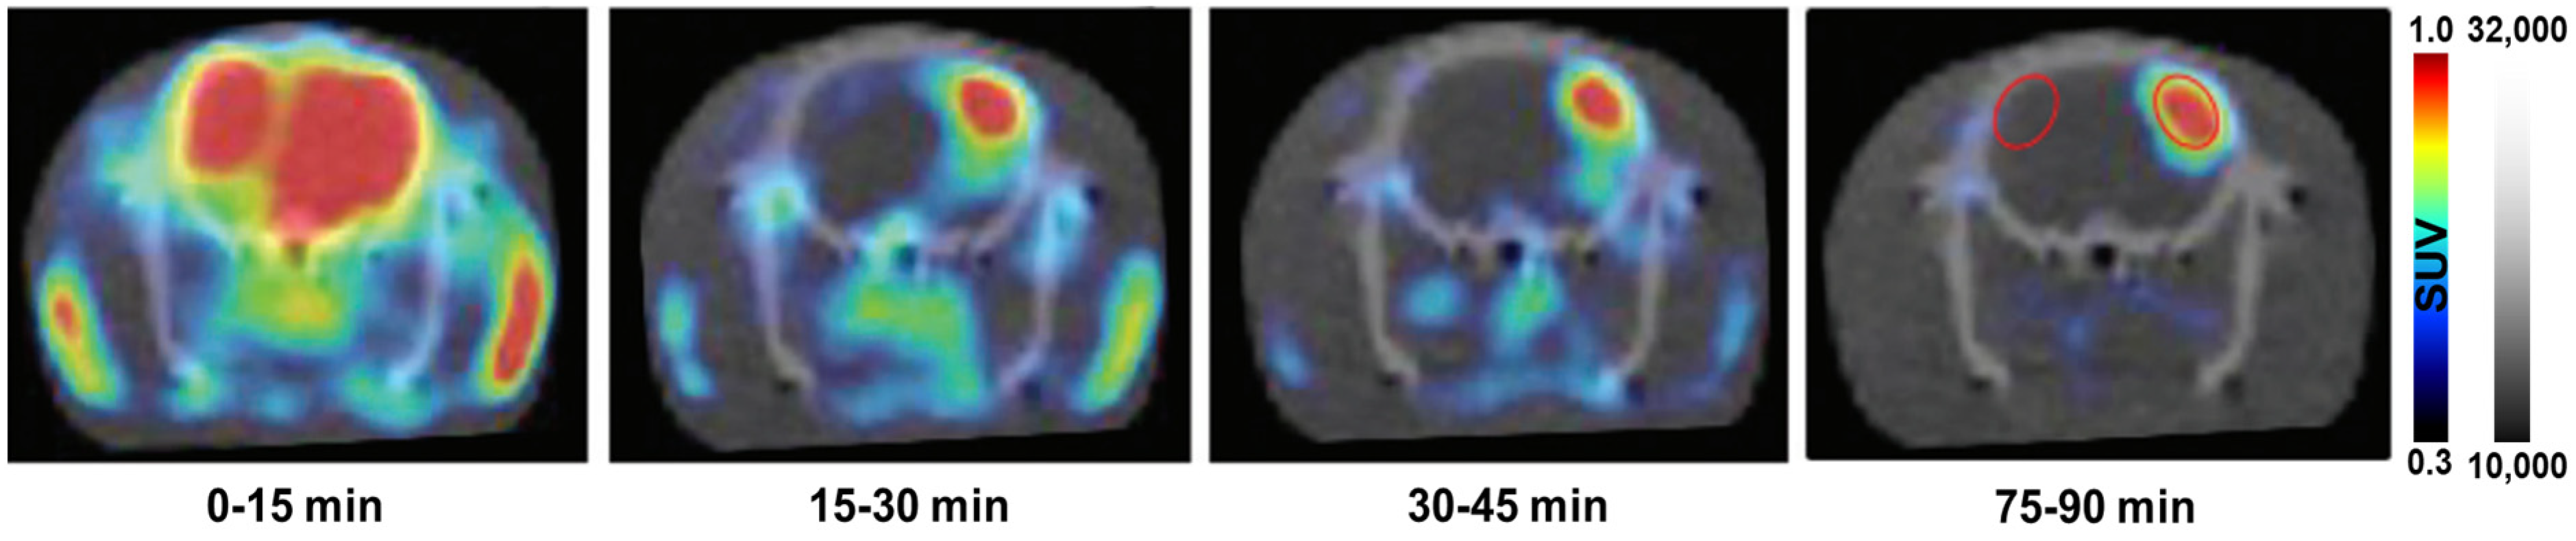

| [18F]KS1 | tumor | In tumor-bearing rats, DOX-induced rats, and tumor-bearing rhesus monkeys, [18F]KS1 showed specific absorption at ROS expression sites. | [30] | ||